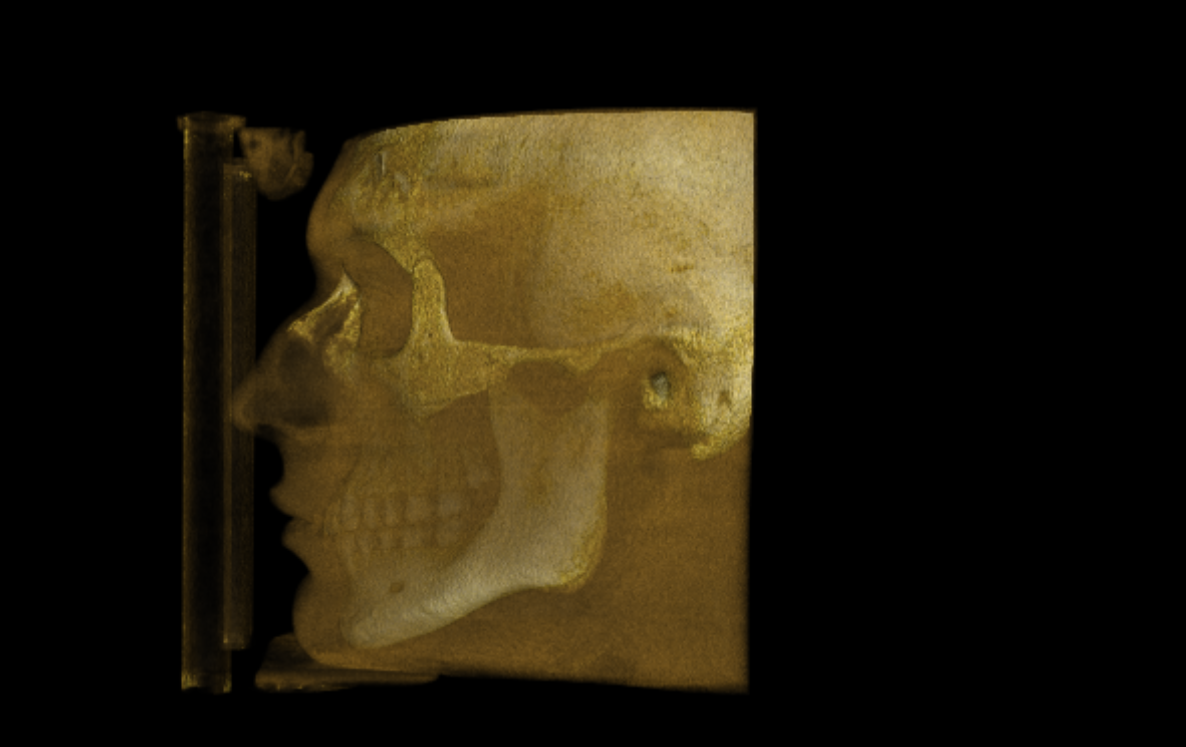

CBCT RENDERS

All attached. Frontal bone, left lateral, right lateral, soft tissue overlays, volume renders at different thresholds. The full skull, nothing hidden, nothing frauded with angles. You can see every problem I just described for yourself.

CBCT RENDERS

All attached. Frontal bone, left lateral, right lateral, soft tissue overlays, volume renders at different thresholds. The full skull, nothing hidden, nothing frauded with angles. You can see every problem I just described for yourself.